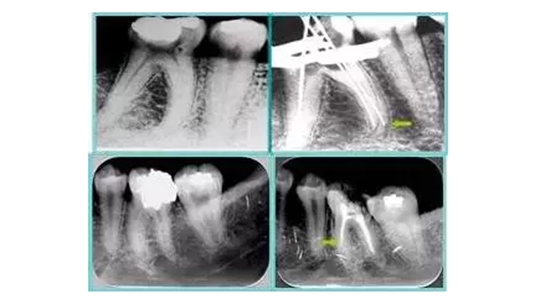

6. 術(shù)后 X 線片

術(shù)后 X 線片用來評(píng)定根管充填 長(zhǎng)度、致密度(管壁清晰、側(cè)枝)等指標(biāo)。

左圖為根管充填術(shù)后 X 線片。圖中可見,根管充填較好。右下圖有白色小點(diǎn),為側(cè)方加壓導(dǎo)致糊劑擠出所致,表明根管充填比較致密。

致密、恰到好處的充填可去除干凈根管里感染灶,機(jī)體逐漸恢復(fù)。

多根牙時(shí)候需進(jìn)行偏移投照,正位投照無法說明具體哪根牙根管充填效果。 二、根管預(yù)備及充填要求